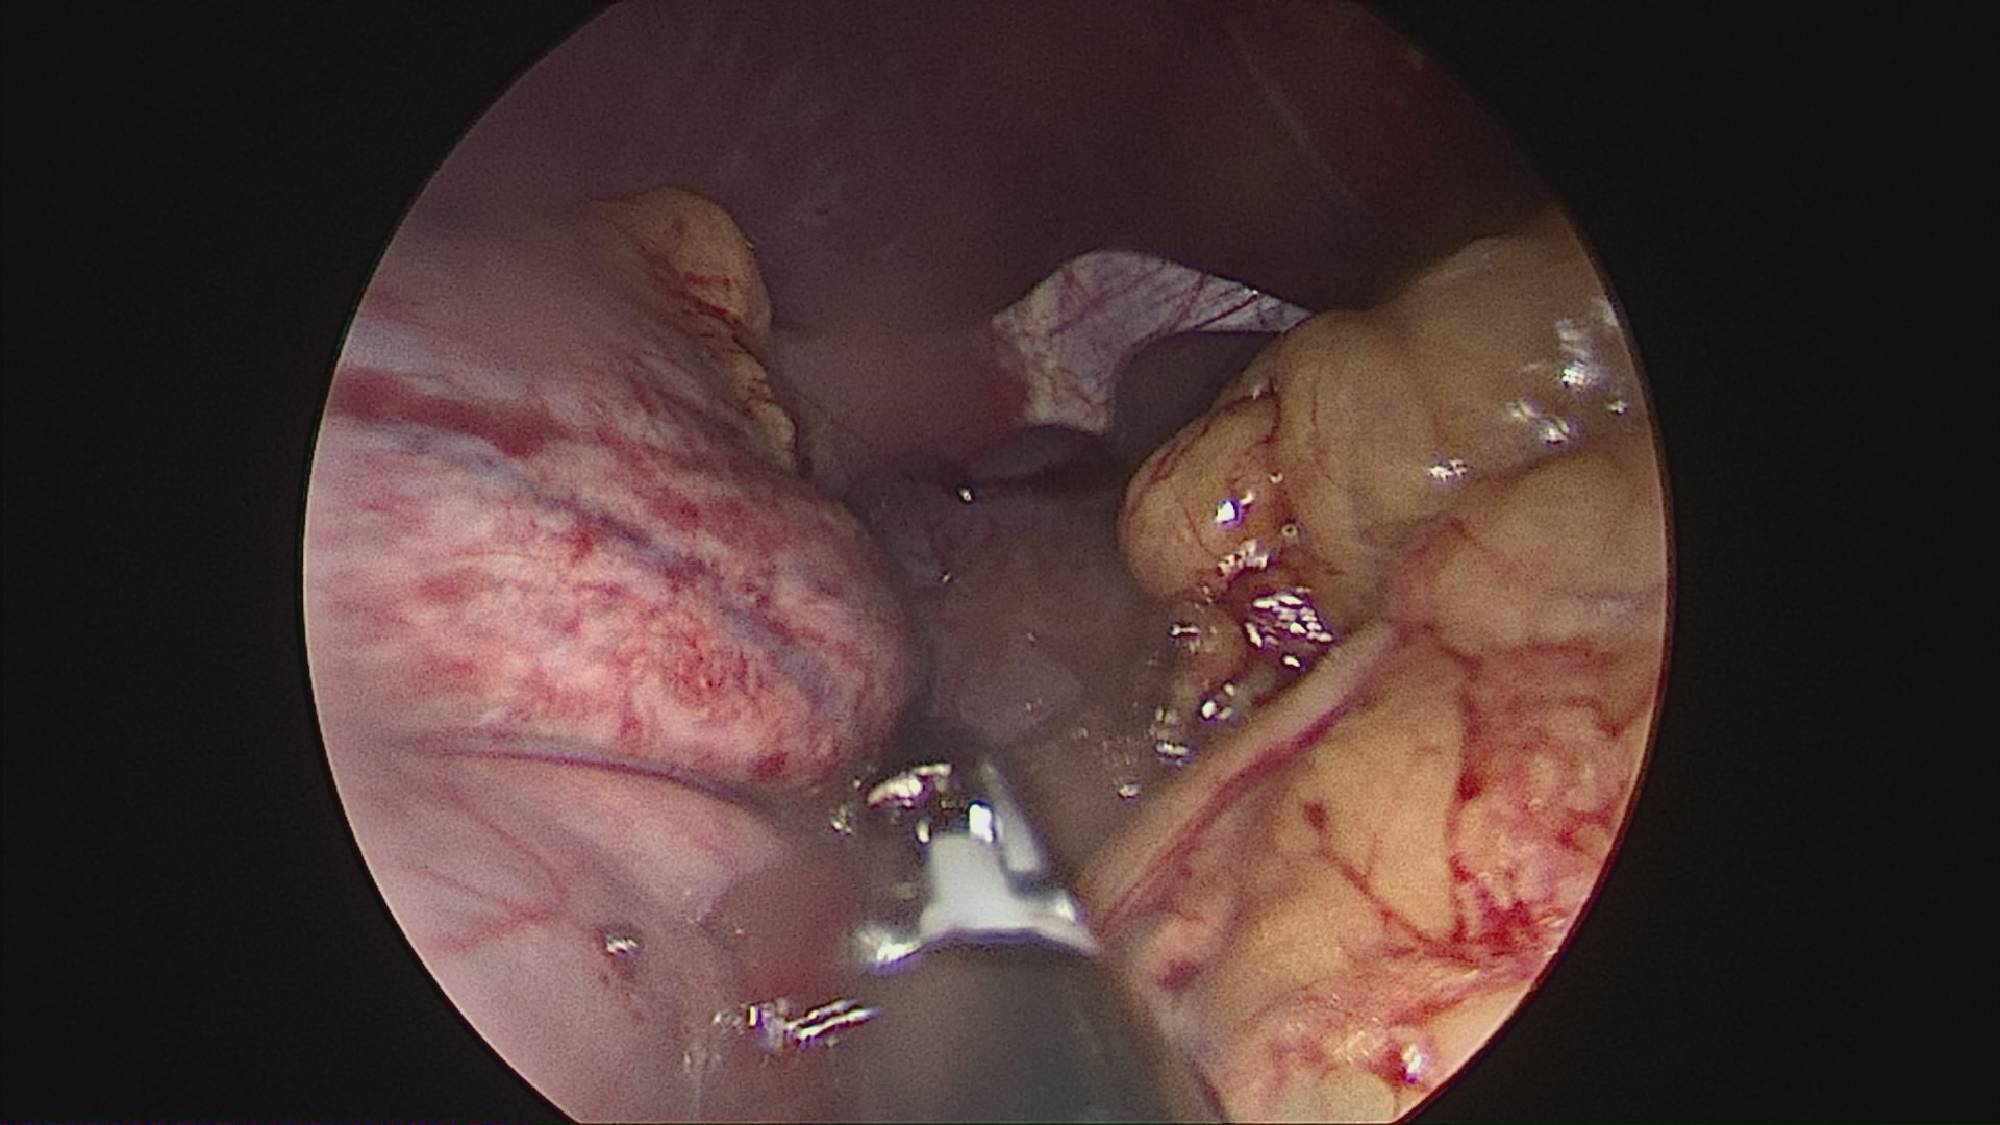

Gastrectomia longitudinală (gastric sleeve) este o intervenție care produce scăderea în greutate prin două mecanisme: restrictiv (îndepărtează o mare parte din stomac lăsând un rezervor de 80-120 ml) și hormonal (prin extirparea fundului gastric se reduce semnificativ secreția hormonului foamei, grelina).

Operația ”de micșorare a stomacului” se realizează miniminvaziv (laparoscopic) și constă în îndepărtarea marii curburi gastrice cu păstrarea antrului gastric și a micii curburi sub forma unui tub calibrat pe o sondă.